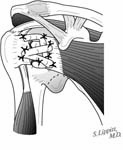

The incision is made in a manner that provides optimal access to the mechanical problem and, if possible, incorporates or respects previous skin incisions. The possible need for extending the incision is anticipated. As shown below, the coracoid is an important landmark when the normal anatomy of the deltopectoral interval is scarred from previous surgery through the anterior approach.

The surgical approach is conducted carefully to protect and preserve the deltoid, the rotator cuff, and the neurovascular structures about the shoulder – each of which may have been altered by previous surgery. The coracoid process serves as a lighthouse for proper orientation in a scarred shoulder. It divides the lateral (safe side) from the medical side (suicide) where the brachial plexus and vascular structures are located (See Figures 1 and 2).